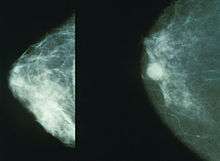

Breast cancer

Higher susceptibility to breast cancer has been found in many studies of rodents and primates exposed to BPA.[78] However, the association between BPA and subsequent development of breast cancer in humans is unclear.[78]